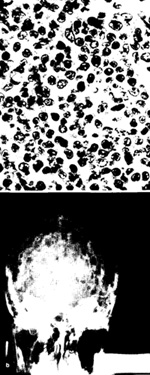

Fig. I. a Posterior auricular lymph node from case 16. An admixture of small and large atypical lymphoid cells is present. Hematoxylin and eosin, X 430. b Plain skull radiograph for case 16. Multiple small lytic lesions are present throughout the calvarium

cases were classified as CTCL, this association is rare since they are the only two out of over 200 cases from the United States, England, and western Europe that were positive for HTL V serum antibodies. As is evident from Table I, the histopathologic diagnoses given vary considerably. There are, however, certain morphologic features shared by most of these tumors. The tissues show diffuse proliferation of a pleomorphic population of lymphoid cells (Fig. I a). The cells tend to vary considerably both in size and shape. In most cases, cells from all points in the spectrum are present in equal proportions, and such cases are designated as diffuse, mixed cell type by both the Rappaport classification and the working formulation [I]. In other cases, one large lymphoid cell type predominates, and such cases are designated as diffusc large cell, or diffuse large cell, immunoblastic lymphoma, based on the characteristics of the proliferating cells. An inflammatory background is normally not evident. The histopathologic features described above are similar to those seen with certain other peripheral T -cell lymphomas not associated with HTL V. Thus, there are no specific pathologic features that can be recognized at this point as indicating an HTL V -associated leukemia/lymphoma. Similarly, there is quite a spectrum in the clinical presentation of cases, which may present a.s lymphoma, leukemia, or lymphoma with leukemic involvement. Some cases appear associated with fulminant and rapidly progressive disease, whereas others have a much more indolent and chronic clinical course. Thus, the exact relationship of HTLV to a specific clinical entity is far from established. Therefore, systematic surveys in HTL V -endemic and nonendemic areas, with special attention to precise immunologic classification of malignant cells, will be needed to clarify thesc relationships further. In addition the recent observation ofantibody-negative, antigen-positive cases of CTCL (C. Saxinger, personal communication) point to a need for caution in defining virus-disease relationships. Ultimately "molecular" epidemiologic studies of defIned disease categories will need to be undertaken before final conclusions can be drawn.

One of the striking features of these cases [4], as well as A TL cases from Japan [20], is the frequent occurrence of idiopathic hypercalcemia. In some cases (Fig. I b) radiographs show multiplc lytic bone lesions mimicking multiple myeloma or metastatic solid tumors. In thesc cases, no lymphoma cells are sccn in association with these lesions but rather osteocla,5t activity and reactive granulation tissue. This pathologic feature may be a reflection of HTL V -activated lymphokine production, although tor cases 4, 16, and 17, the lymphokine, osteoclast activating factor (OAF) was not detectable in bioassay [3]. A variety of lymphokines are produced by HTLV-infected cell lines in vitro, suggesting that integration of proviral DNA results in derepression of host genes including those tor various lymphokines [8]. Viral-associated cases with hypercalcemia provide a convenient setting to test this model.